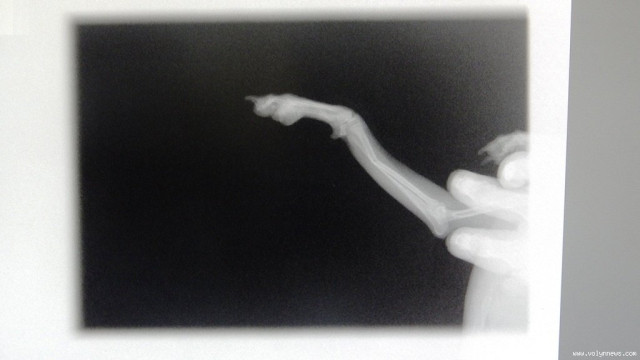

Господарка собачки на прізвисько Бублик, породи мопс, каже, що свого песика привела на рентген та УЗД. Жінка запевняє, їй не шкода ніяких грошей на лікування свого улюбленця, головне - щоб її пес був живим та здоровим. Вона від щирого серця дякує працівникам клініки за їхню роботу і вітає з Днем ветеринара. Адже жінка переконана, що професія ветеринара потрібна не менше, ніж медик – для людини.

Зі слів лікаря, ветеринарна медицина у Луцьку процвітає. Наші лікарі переймають сучасні методи лікування. Тетяна Шопулко також зазначила, що у їхній клініці є все необхідне обладнання для діагностування та лікування пацієнтів. Зокрема у них є рентген апарат, обладнання, яке робить загальний аналіз крові і апарат, який робить УЗД (ультразвукове дослідження).